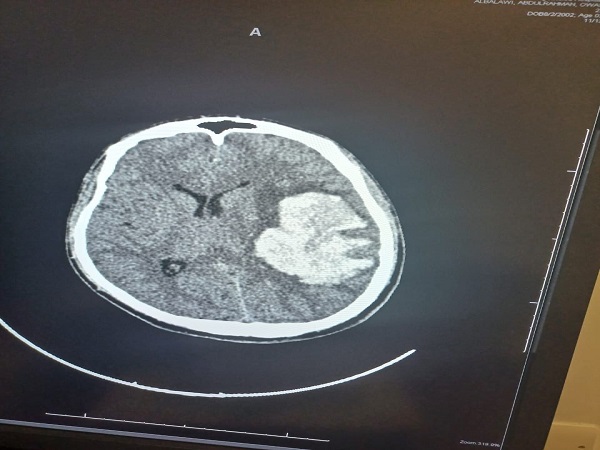

تمكن بفضل من الله فريق طبي من قسم جراحة المخ والاعصاب بمستشفى الملك خالد التابع للتجمع الصحي بتبوك من انقاذ حياة شاب بالعشرين من عمره وصل الى قسم الطوارئ وهو في حالة فقدان للوعي وبعد عمل الفحوصات اللازمة وتصوير الاوعية الدموية الدماغية تبين وجود نزيف دماغي حاد في الجهة اليسرى كذلك وجود تشوه خلقي دموي وعائي كبيرا جدا.

وأوضح الفريق الطبي من قسم جراحة المخ والاعصاب بالتجمع بانه تم فورا ادخال المريض الى غرفة العمليات واجراء استئصال للأوعية الدموية مجهريا حيث استغرق اجراء العملية أكثر من 5 ساعات تكللت ولله الحمد بالنجاح كما تم تحويل المريض لقسم التنويم بمتابعة وإشراف الفريق الطبي.

واكد الفريق الطبي بان حالة المريض تحسنت تدريجيا ولم تكن هناك أي مضاعفات اثناء وبعد العملية وبدا بحركة الأطراف إضافة الى فتح العينين ولله الحمد.